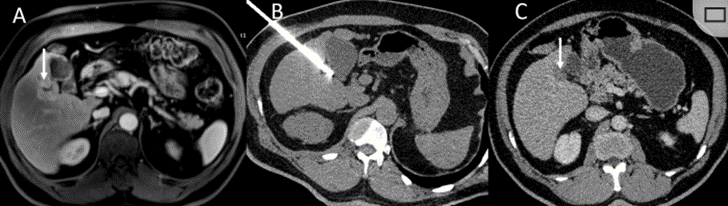

冷冻消融胆囊附近肿瘤病灶

(A)动脉期 MRI 显示胆囊附近有外周增强病变(箭头)。

(B)手术过程中 CT 显示冷冻探针位于病灶内。

(C)消融后,术后 1 个月CT 显示完全消融(箭头)。